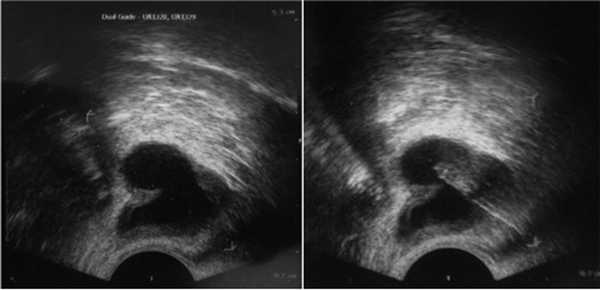

В анализе спермограммы - без патологии. Принято решение выполнить пункцию кисты правого семенного пузырька под местной анестезией под контролем ТРУЗИ (рис. 6). Рисунок 6. Пункция кисты правого семенного пузырька пациента В. под контролем ТРУЗИ. В ходе пункции эвакуировано около 25 мл жидкости «шоколадного» цвета.

По данным УЗИ, в проекции левого семенного пузырька выявлена киста объемом около 20 см 3 . Под контролем ТРУЗИ выполнена пункция кисты, эвакуировано около 15 мл жидкости «шоколадного» цвета (рис. 8). Рисунок 8. Пункция кисты правого семенного пузырька пациента C. под контролем ТРУЗИ.